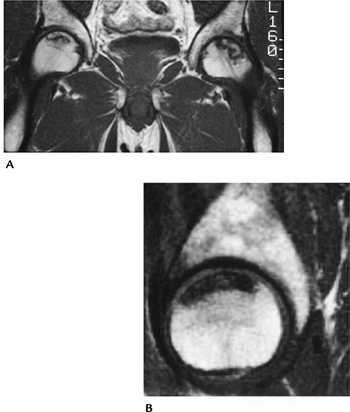

a8b6860d311652176283f3b390b744ca.png

图-8嗜酸性肉芽肿。(A)股骨的前后位X光片显示一个溶骨性病变,伴有骨内膜扇贝样侵蚀和骨膜反应。脊柱的前后位(B)和侧位(C)X光片显示T6椎体明显的压缩(扁平椎)。